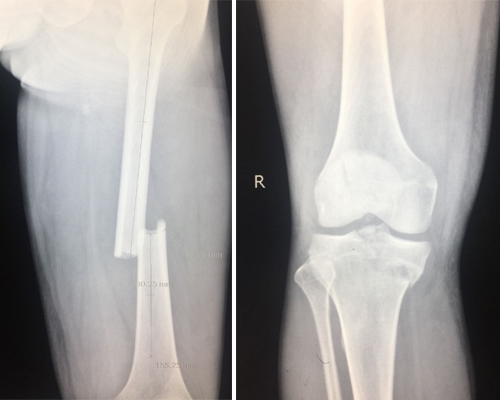

检查拍片显示:右股骨中段骨折、右胫骨上段粉碎性骨折、右髌骨粉碎性骨折、右侧眼眶内侧壁骨折。